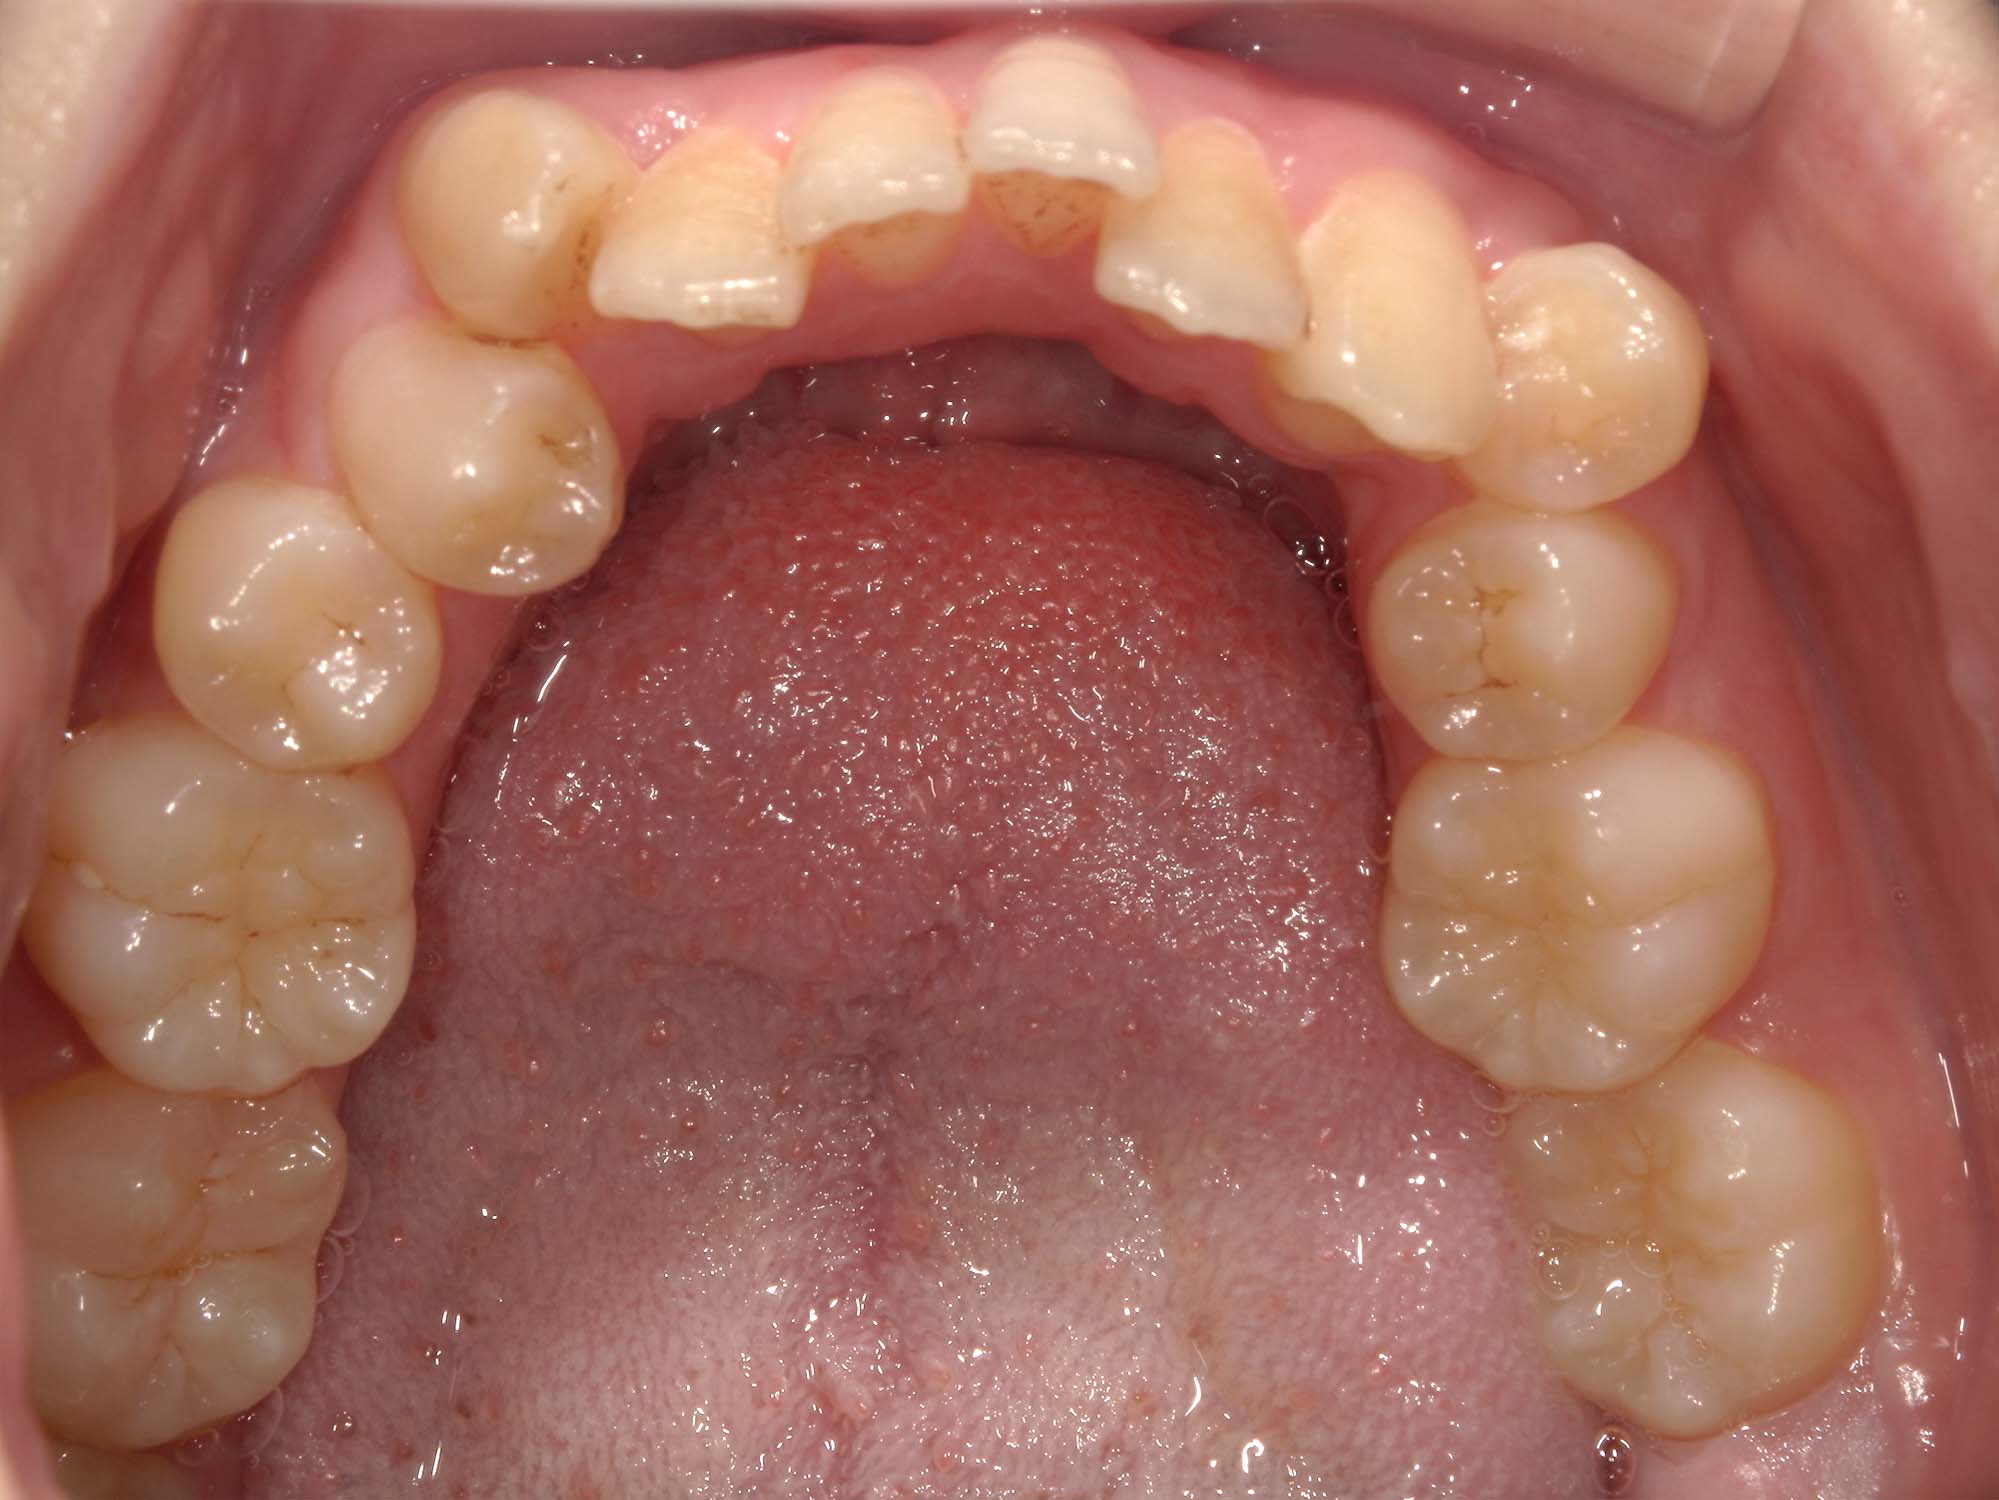

| 年齢・性別 | 22歳女性 |

|---|---|

| 主訴 | 上下顎前歯部に開咬と口元の突出感を気にされて来院された22歳女性。咬み合わせや審美的な改善を希望されていました。 |

| 治療期間・回数 | 3年9ヶ月・32回 |

| 費用 | 930,000円 |